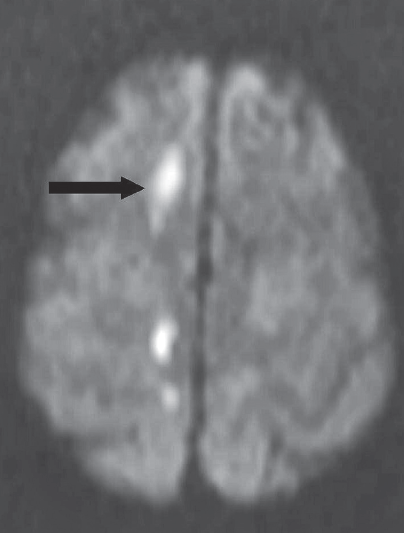

Laboratory tests. MRI scans of the head revealed acute infarcts (arrows) in the right corona radiata, right centrum semiovale, and anterior and posterior corpus callosum.

Discussion. The diagnosis based on neurological consultation was alien hand syndrome, which is the loss of control of 1 or both upper extremities when the involuntary movements of the affected extremity are not caused by a movement disorder.1 Several anatomical lesions have been identified as causes: the corpus callosum alone, the corpus callosum plus the dominant medial frontal cortex, and the posterior cortical and subcortical regions. The posterior form of the syndrome typically results from corticobasal degeneration or from a cerebrovascular accident.2 The anterior forms are associated with anterior cerebral artery territory infarction.